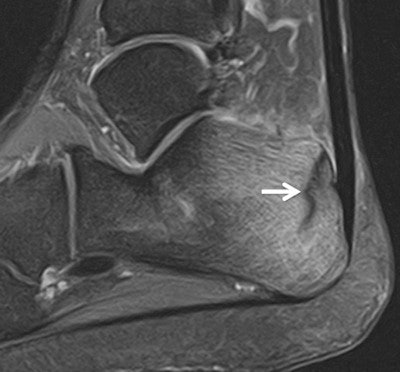

However, in the run to the games they have seen several typical sports injuries, including a fatigue stress fracture in the heel of a long distance runner and a case of iliotibial band syndrome in the knee of a hockey player (see images).

Male long-distance runner, 22, with a two-week history of heel pain. Sagittal T2-weighted fat-saturated image (Toshiba, Elan 1.5-tesla) shows linear hypointensity (arrow) in the posterior calcaneus and diffuse high signal intensity in the adjacent marrow in keeping with a recent incomplete fatigue stress fracture with surrounding marrow edema. All images courtesy of Dr. David Ritchie.